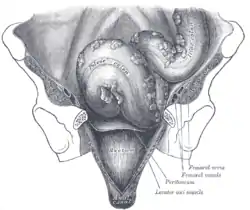

Iliac colon, sigmoid or pelvic colon, and rectum seen from the front, after removal of pubic bones and bladder. (Lumps of fat visible at right.) | |